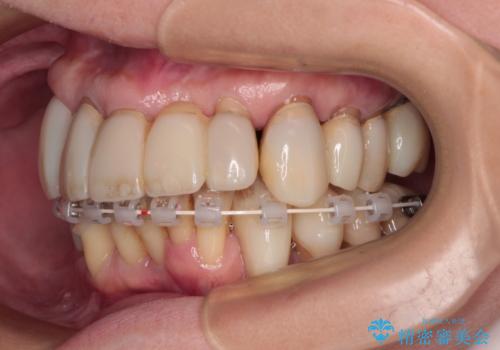

- 矯正装置

- 審美装置

2~3年は早く終了する予定でしたが、途中で体調を崩されて来院されない時期が続いたため、非常に長期間の治療となりました。

上顎口蓋からの堅い歯肉を移植する角化歯肉移植術を行いたかったのですが、体調不良から実施しなかったため、最終補綴物であるオールセラミッククラウンを装着した後に、知覚過敏や境目が見てしまうといった問題が一部で発生いたしました。